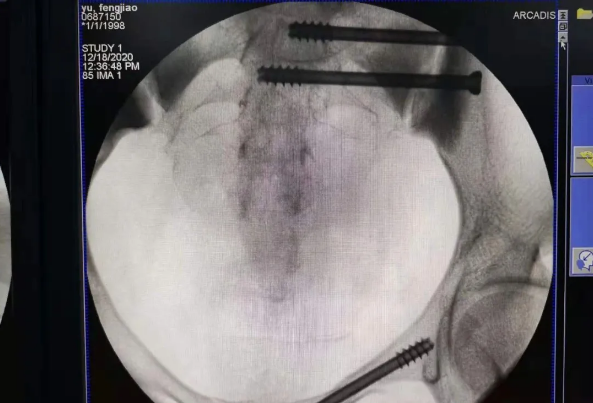

由于天玑?骨科手术机械人的精准及高效,,,,,可以使手术时间显着缩短,,,,,因此在骨盆骨折手术后,,,,,在廖琦教授指导下,,,,,脊柱外科团队使用天玑?骨科手术机械人同样为20岁女性腰椎骨折患者“量身定做”最理想、最清静的教科书般的通道,,,,,完善清静微创完成手术,,,,,手术不但时间缩短,,,,,并且出血和透视镌汰。。。。。。